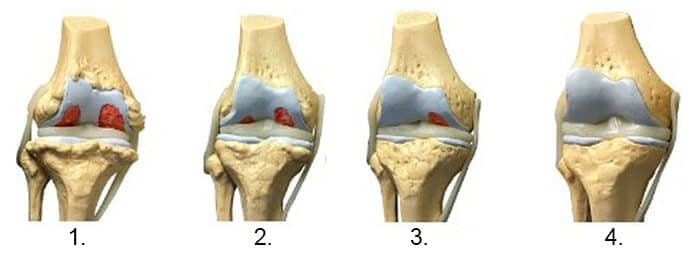

1. Недостаток на исхрана во зглобот. Ткивото на 'рскавицата се уништува.

2. Обновување на 'рскавичното ткиво на зглобот после 2 недели употреба на Arthro Blue.

3. Обновување на 'рскавичното ткиво на зглобот по 3 недели употреба на Arthro Blue.

4. Здрав зглоб по еден третман на лекување со Arthro Blue.

– Рендгенските снимки подолу ја покажуваат типичната слика за заздравувањето на зглобот на коленото.